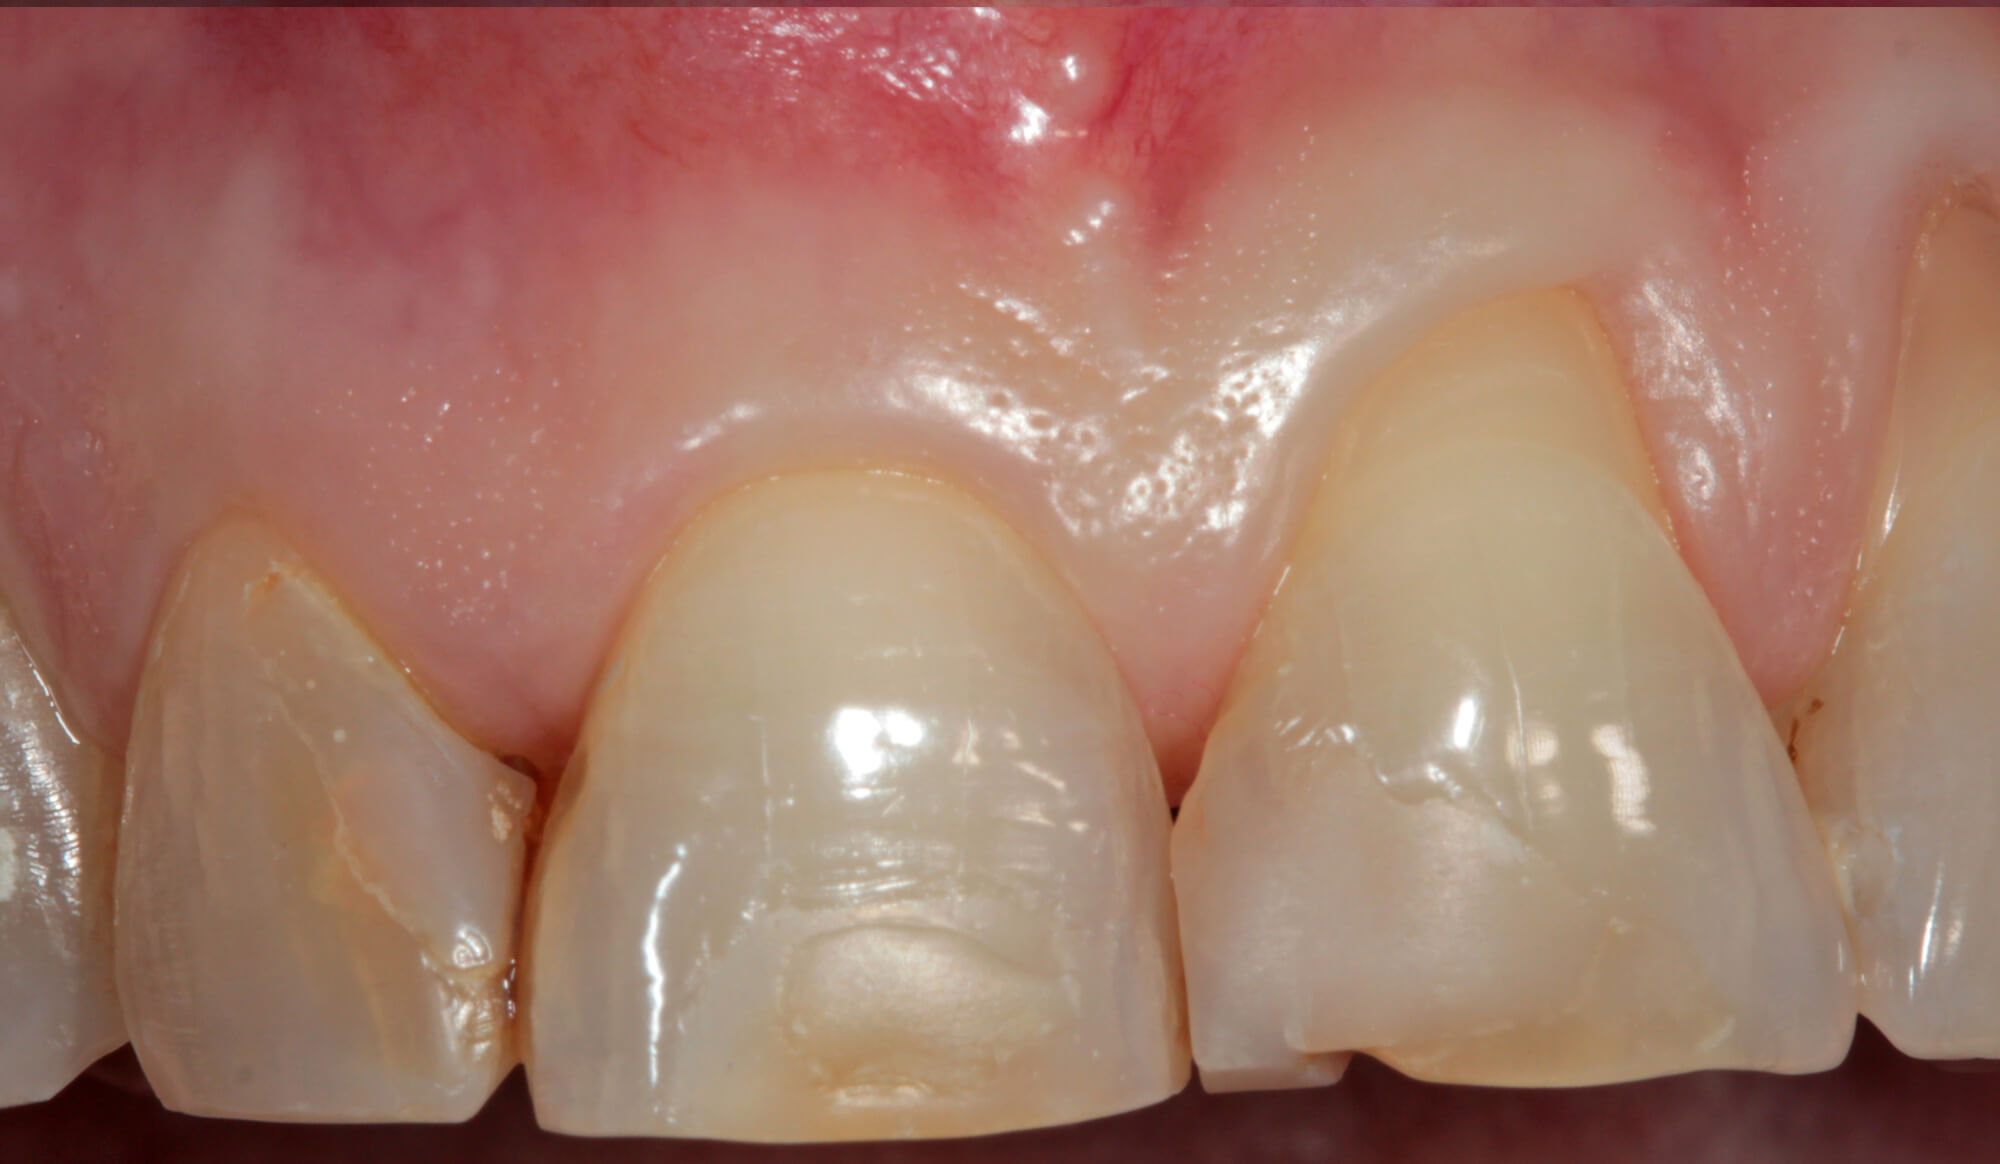

Faccetta estetica prima di essere applicata sul dente

Faccette Estetiche

In odontoiatria le faccette estetiche sono sottili lamine di ceramica o di resine composite che vengono applicate sulla superficie di denti sani per modificarne aspetto, colore e forma, talvolta anche per modificare parametri occlusali.

Questo è uno dei metodi di restauro dentale che richiede una preparazione minimale dei denti. L’unione fra dente e faccetta avviene mediante un cemento resina composito.

Le faccette quindi possono risolvere con un trattamento veloce e poco invasivo problematiche di tipo estetico che posso causare problemi anche emotivi soprattutto in pazienti giovani che da molti anni sono condizionati da denti pigmentati, o più piccoli del normale (conoidi), che influiscono sulla capacità di relazione con gli altri ragazzi.